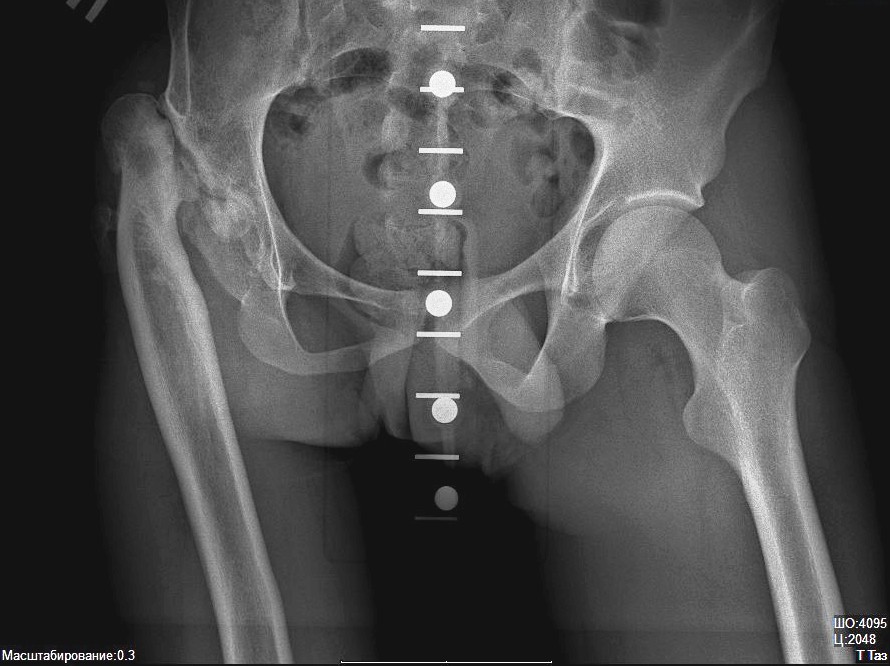

Анкилозом могут быть поражены такие мелкие и крупные суставы:

- Тазобедренный.

Рассмотрим, какие еще способы лечения используются при анкилозе левого и правого тазобедренного сустава:

- Терапия медикаментами – антибактериальными, нестероидными противовоспалительными и обезболивающими средствами.

- Комплексная ортопедическая терапия.

- Лечебная гимнастика.

- Массаж и мануальная терапия.

- Физиотерапевтические процедуры.